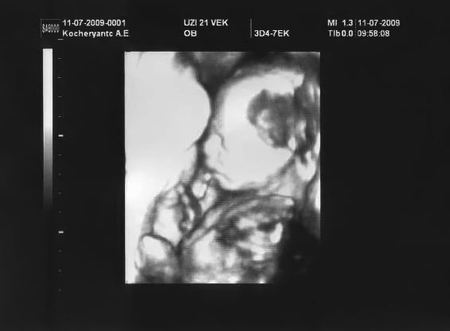

а это нам уже 22 недели

и сегодня нам показали нашу красотку..))